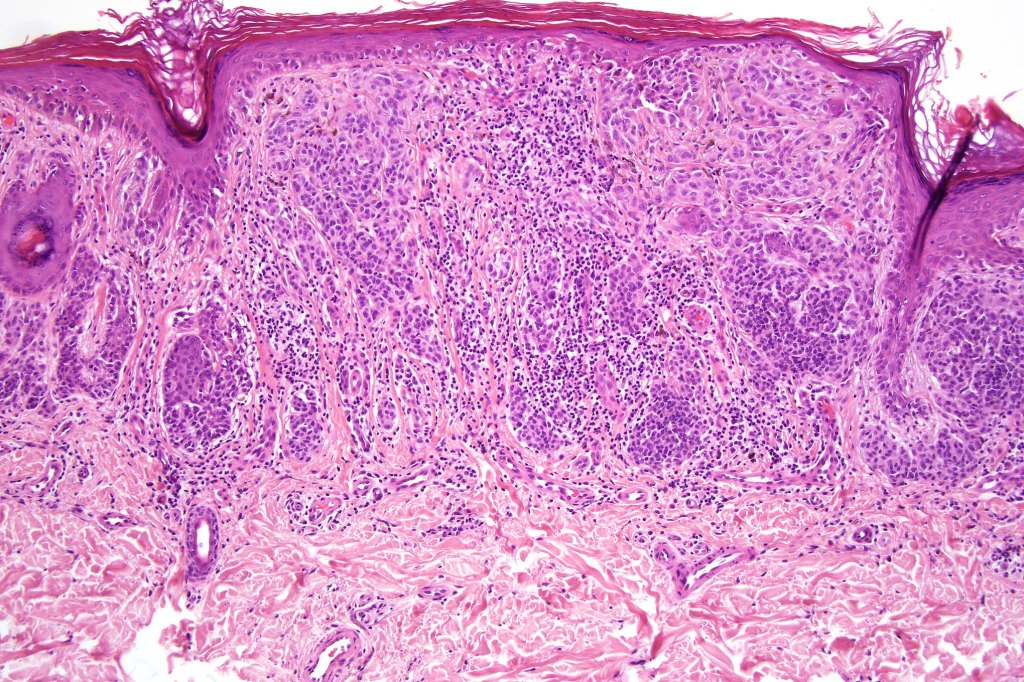

Combined congenital & blue nevus (same case as the clinical photographs coursty of Dr. Antonina Kalmykova